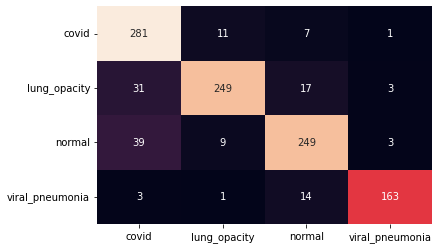

III.2 Classification results

The training procedure in all scenarios has converged. Looking at the evolution of training and validation accuracy (Fig. 11a) indicates that a larger validation dataset would be beneficial. To stabilise the classifier training a procedure of multiple training runs to select the best model is used (Materials and methods). Resulting classifiers are able to discriminate between classes with good precision, for example, see the confusion matrix of the best overall model presented in Fig. 11b. It can also be seen that for the normal class, the rate of misclassified images as COVID-19 ones is higher than for other classes. This effect is present for all models although smaller for the ones based on the EfficientNet-B0 architecture. In addition, the EfficientNet-B0 variants excel if the correct classification of viral pneumonia class images with the smallest rate of errors. However, the EfficientNet-B0 GAN augmentation scenario shows increased misclassification of healthy images which leads to a poor performance. The evolution of the training accuracy as well as confusion matrices for all models are summarised at the end of this section.

Training results for the two architectures are summarised in Figs. 13, 14, 15, 16, and Table 3. For each architecture four scenarios are considered as described in Training process part of the Materials and methods Section.